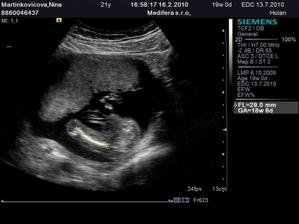

♥ 16.2. (utorok) ideme na 4D ultrazvuk!! 🙂 - Boli sme, nádherný zážitok!!! Je to chlapec ako sa patrí, úplne zdravý a krásny!!! 🙂 4D nám lekár ukázal len nožičky a pipíka, lebo tvárička nie je dobre vidieť tak skoro, ale to vôbec nevadí... 🙂